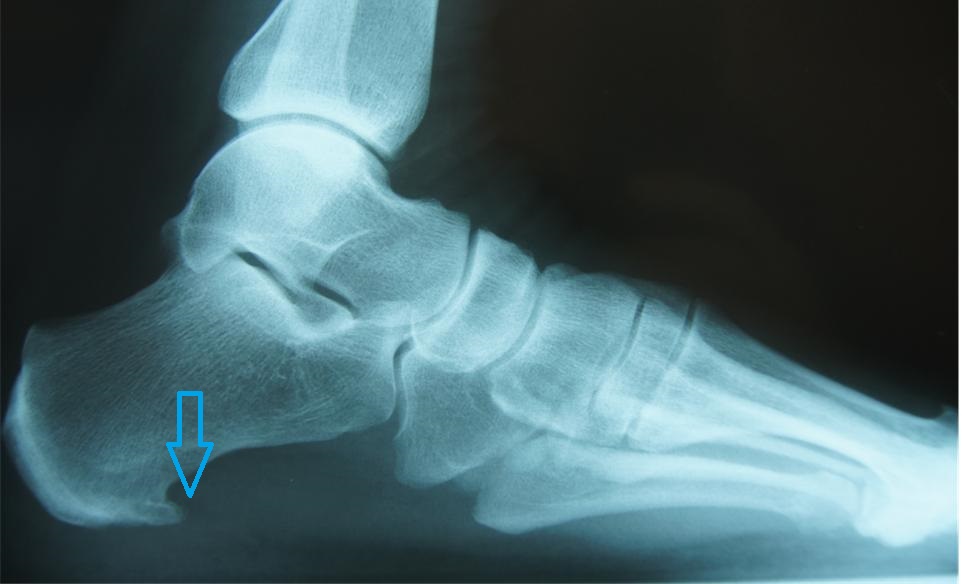

Hielspoor

Verkalking onder het hielbeen, meestal thv het begin van de peesplaat

Hielspoor is een verkalking van de peesplaat aan het hielbeen. 15 tot 20% van de mensen loopt rond met een hielspoor aan beide voeten maar klaagt hier niet over. Hielspoor kun je met een röntgenfoto of met echografie diagnosticeren. Hielspoor ontstaat omdat trekspanning aan de peesplaat onder de voet na vele jaren (50 à 60 jaar) een reactie kan geven aan het hielbeen met een hielspoor als resultaat. Deze hielspoor is meestal onschuldig. Deze kan alleen operatief verwijderd worden, maar omdat er een zeer belangrijke peesplaat zit is dit af te raden.